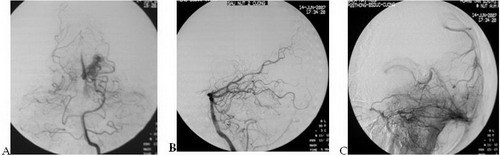

Trường hợp 1: tổn thương nằm sâu cạnh não thất

Hình 1: Bệnh nhân nam, 37 tuổi, đau đầu 1 năm, vào viện do đau đầu nhiều; chụp CLVT (08.07.07) xuất huyết não thất, chụp CHT (13.06.07) thấy DDĐTMN cạnh sừng chẩm não thất bên trái (vùng đồi thị); chụp mạch (18.05.07) (a): ổ dị dạng kích thước nhỏ 1 x2cm, nằm vùng não sâu cậnh đường giữa sau, có những cuống nuôi nhỏ là ĐM mạch mạc từ ĐM não sau trái, tĩnh mạch dẫn lưu sâu (Spetzler-Martin III) (a). Nút mạch (14.06.07), gây tắc 2 cuống nhỏ: cuống 1 bơm 0.5ml với tỷ lệ Histoacryl/Lipiodol: 0.5ml/2.0ml, cuống 2 bơm 0.2ml với tỷ lệ 0.5ml/2.5ml; chụp kiểm tra sau nút trên tư thế nghiêng thì động mạch (b) và thì tĩnh mạch (c) thấy tắc hoàn toàn ổ dị dạng.